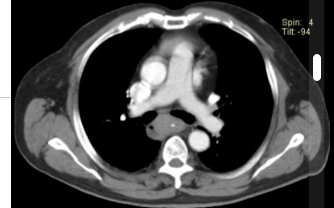

Aumento do tronco da artéria pulmonar

Estenose congenita da valva pulmonar.